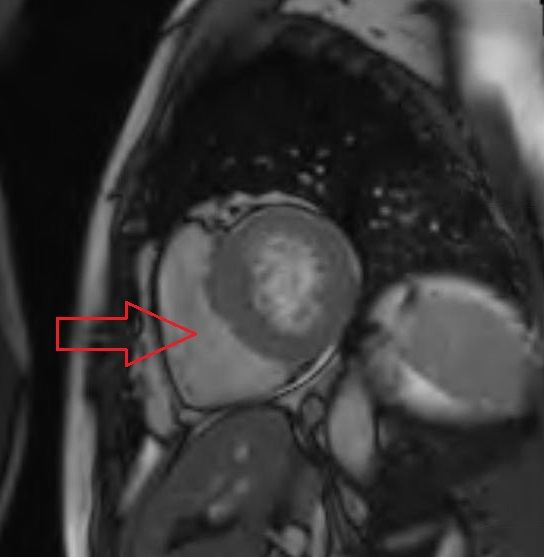

13. Name the arrowed structure